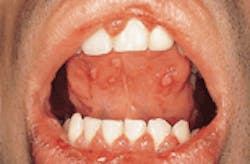

Acute Herpetic Gingivostomatitis

2. Identify which of the following signs and symptoms are characteristic of acute herpetic gingivostomatitis that is subclinical:

3. Identify the location(s) of the oral lesions seen with acute herpetic gingivostomatitis:

4. Identify the method(s) used to diagnosis acute herpetic gingivostomatitis: